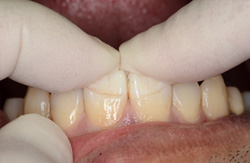

もってきた折れた歯冠の戻り具合(位置、方向)をまず確認します。 |